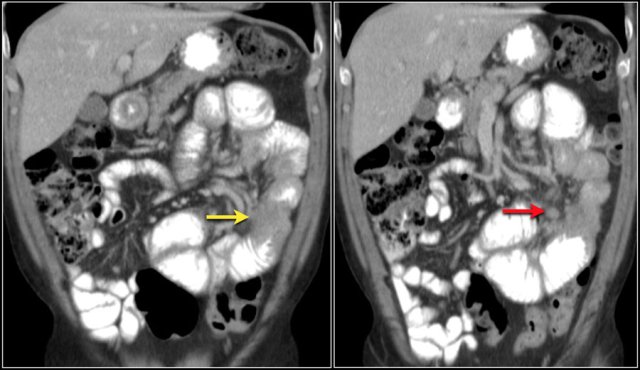

The images show a carcinoid tumor presenting as a hypervascular mass (red arrow) with desmoplastic reaction (yellow arrow).